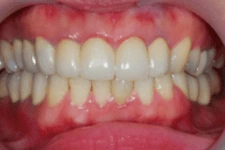

↑ 治療後:微創立即植牙恢復美麗外觀